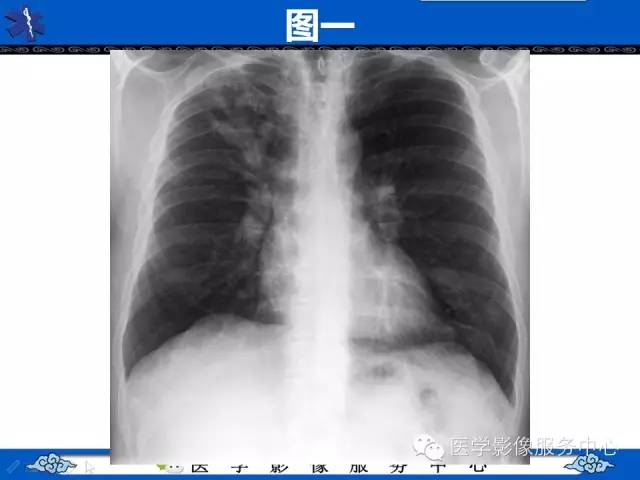

【病例】胸壁弹力纤维瘤1例CT影像表现